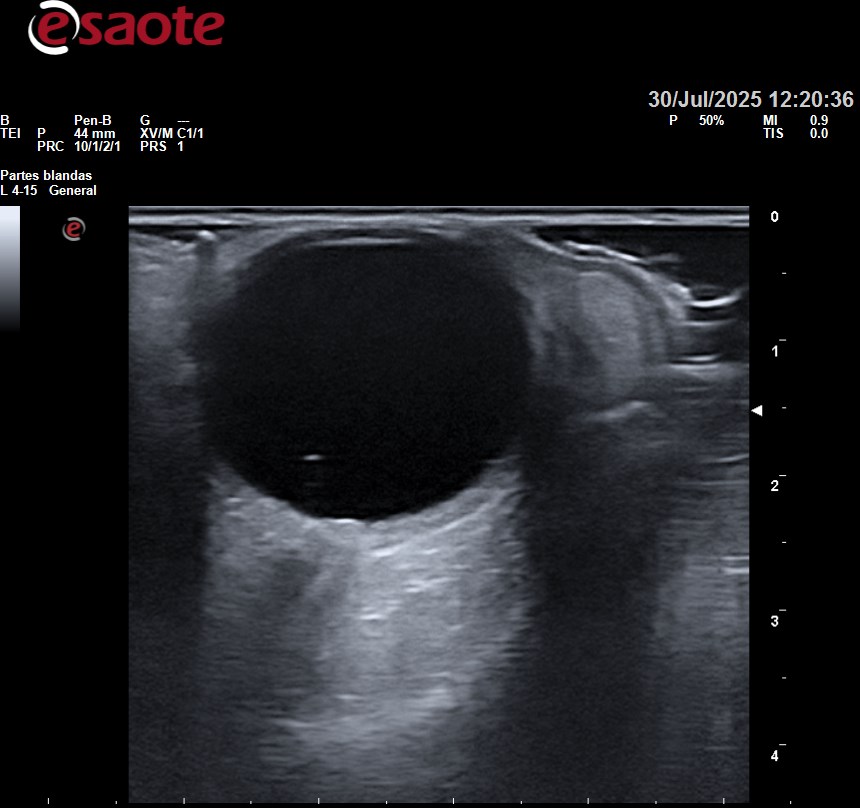

Se realiza una Ecografía ocular.

Hallazgos ecográficos

Cornea, cámara anterior, iris y cristalino sin alteraciones de interés.

Se realiza barrido del globo ocular en corte longitudinal, transversal y con movimientos oculares. Observándose un punto y líneas hiperecogénicas flotando en vítreo desplazándose con movimientos oculares.

Exploración de nervio óptico sin presentar alteración estructural y con captación de doppler normal.